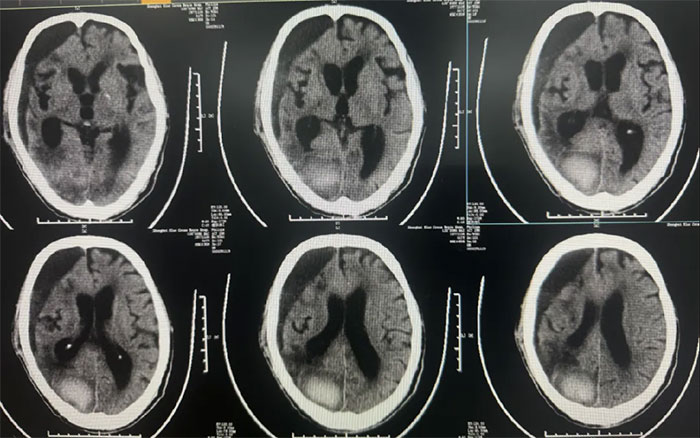

● 硬膜下血腫引流15天后拔管,中線基本復位,硬膜下血腫較前明顯減少;

● 患者神志昏迷,自動睜眼,無發(fā)聲,肢體刺痛躲避。GCS評分:9分;

● 無明顯顱內(nèi)感染,生命體征平穩(wěn)。